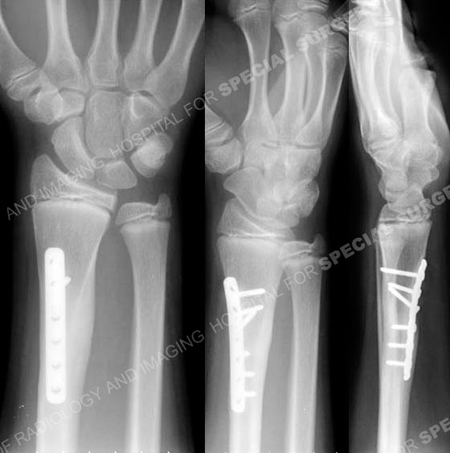

Anteroposterior and lateral radiographs 8 months following fracture surgery illustrating a healed distal radius fracture in excellent alignment.